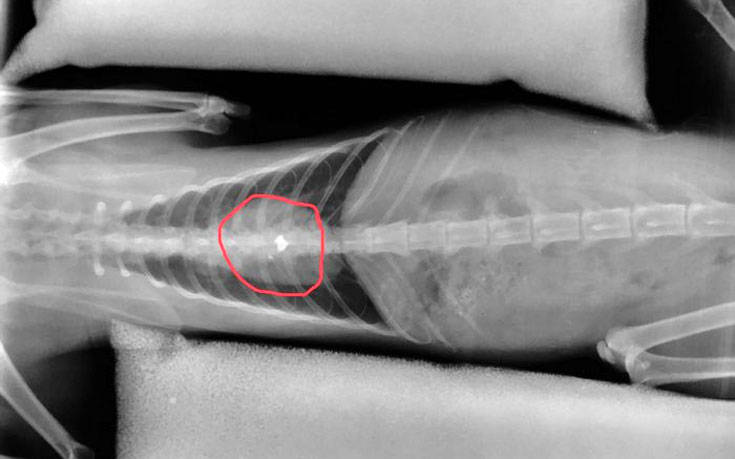

Σύμφωνα με τα όσα κατατέθηκαν ενώπιον των αστυνομικών και δικαστικών αρχών, ο εκπαιδευτικός που είναι και Λυκειάρχης σε σχολείο του δήμου Λαμιέων, πυροβόλησε το άτυχο ζώο με αεροβόλο, με τη βολίδα να σφηνώνεται στη σπονδυλική του στήλη και να μένει παράλυτο.

«Σε 16 μήνες φυλάκιση καταδικάστηκε σήμερα 12 Ιουλίου 2019 εκπαιδευτικός, διευθυντής σε Λύκειο της Δευτεροβάθμιας Εκπαίδευσης του Δήμου Λαμιέων, ο οποίος εν ψυχρώ πυροβόλησε και άφησε παράλυτο από την μέση και κάτω έναν αδέσποτο γάτο. Το άτυχο ζώο πυροβολήθηκε από τον δράστη με αεροβόλο όπλο την ώρα που ζευγάρωνε.